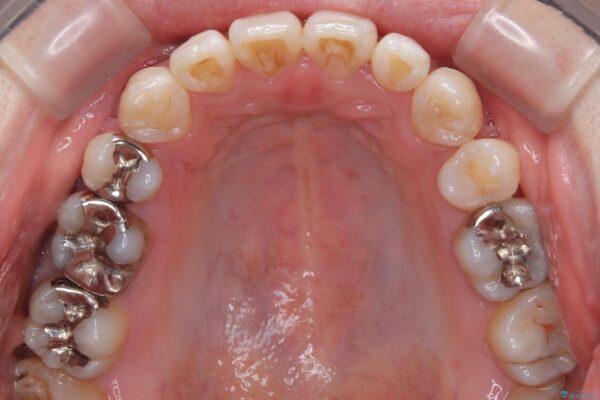

少しずつ前歯を後ろに下げていくことで、横顔のラインが整い、口元の“出っ張り感”が解消。

治療後には「自然に笑えるようになった」と嬉しいお声をいただきました。

治療後

• 口元の突出感を改善!目立ちにくいワイヤー矯正で自信を持てる自然な横顔に 治療後画像